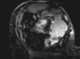

Mural hemorrhage